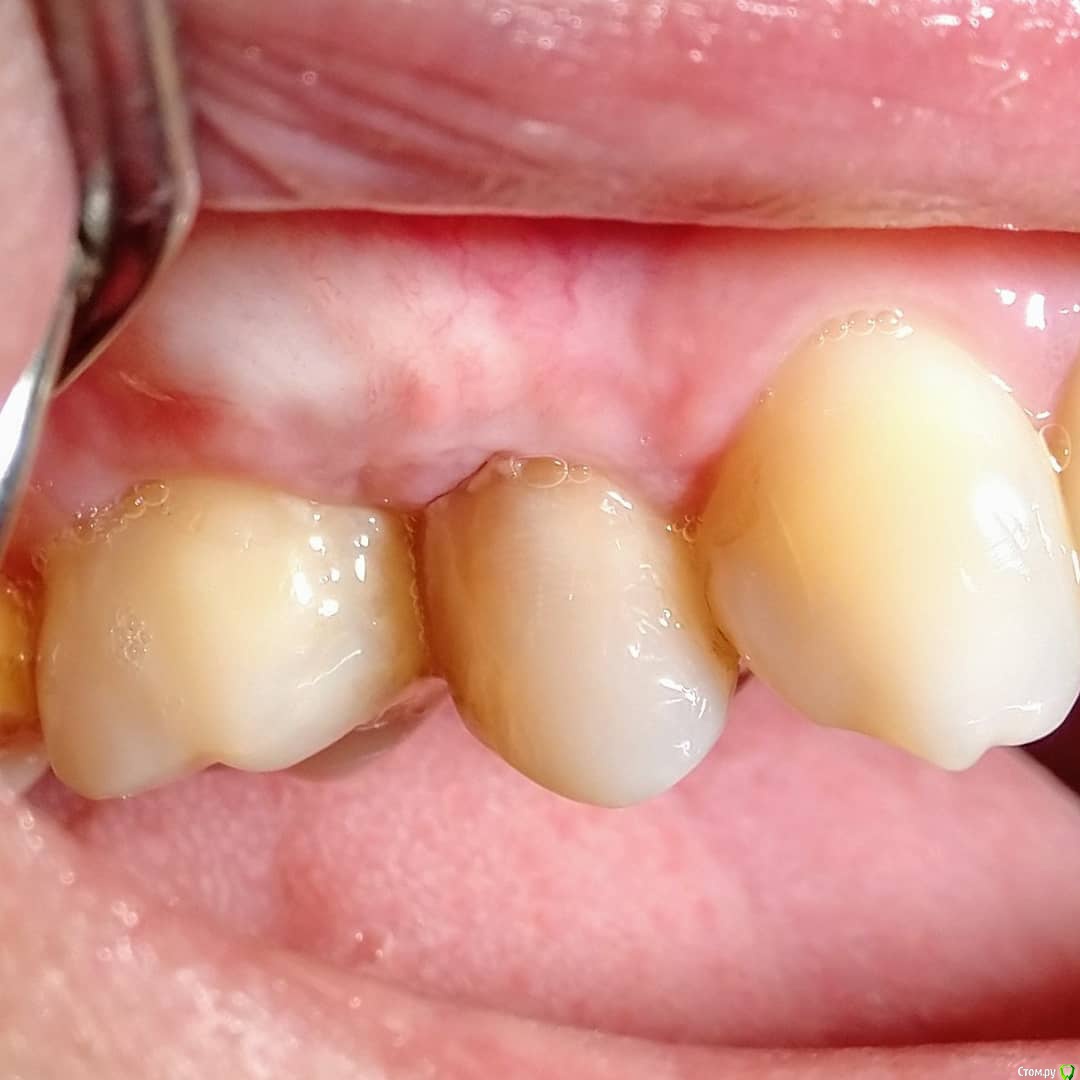

Отрезала бугор, огромный ломоть, получили толщину тканей феерическую, с избытком таким, что глаз дергался, глядя на этот Эверест (второе фото). Гулять так гулять, подумала я и сделала следующее (на схеме) - расслоила этот бугор, сделав разрез выше края десны, все вокруг деэпителизировала, мобилизовала и натянула. И оно таки сработало! Последнее фото - 6 месяцев результату, продолжаем наблюдать. post-35757-0-84941800-1532674651_thumb.jpgpost-35757-0-82539900-1532674591_thumb.jpgpost-35757-0-09882000-1532674698_thumb.jpgpost-35757-0-47621300-1532674725_thumb.jpgpost-35757-0-64948100-1532674747_thumb.jpg